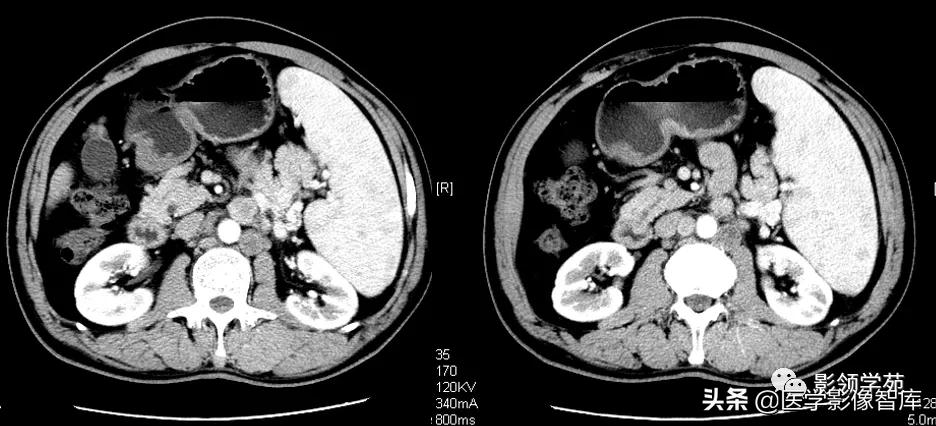

- CT平扫脾门部小结节,多数直径不超过2.5cm,边缘光滑。偶见位于脾门以外者。

- 增强扫描副脾与主脾强化一致,CT值相同。

- 动态增强扫描:两者的增强与消退之动态变化也完全一致。